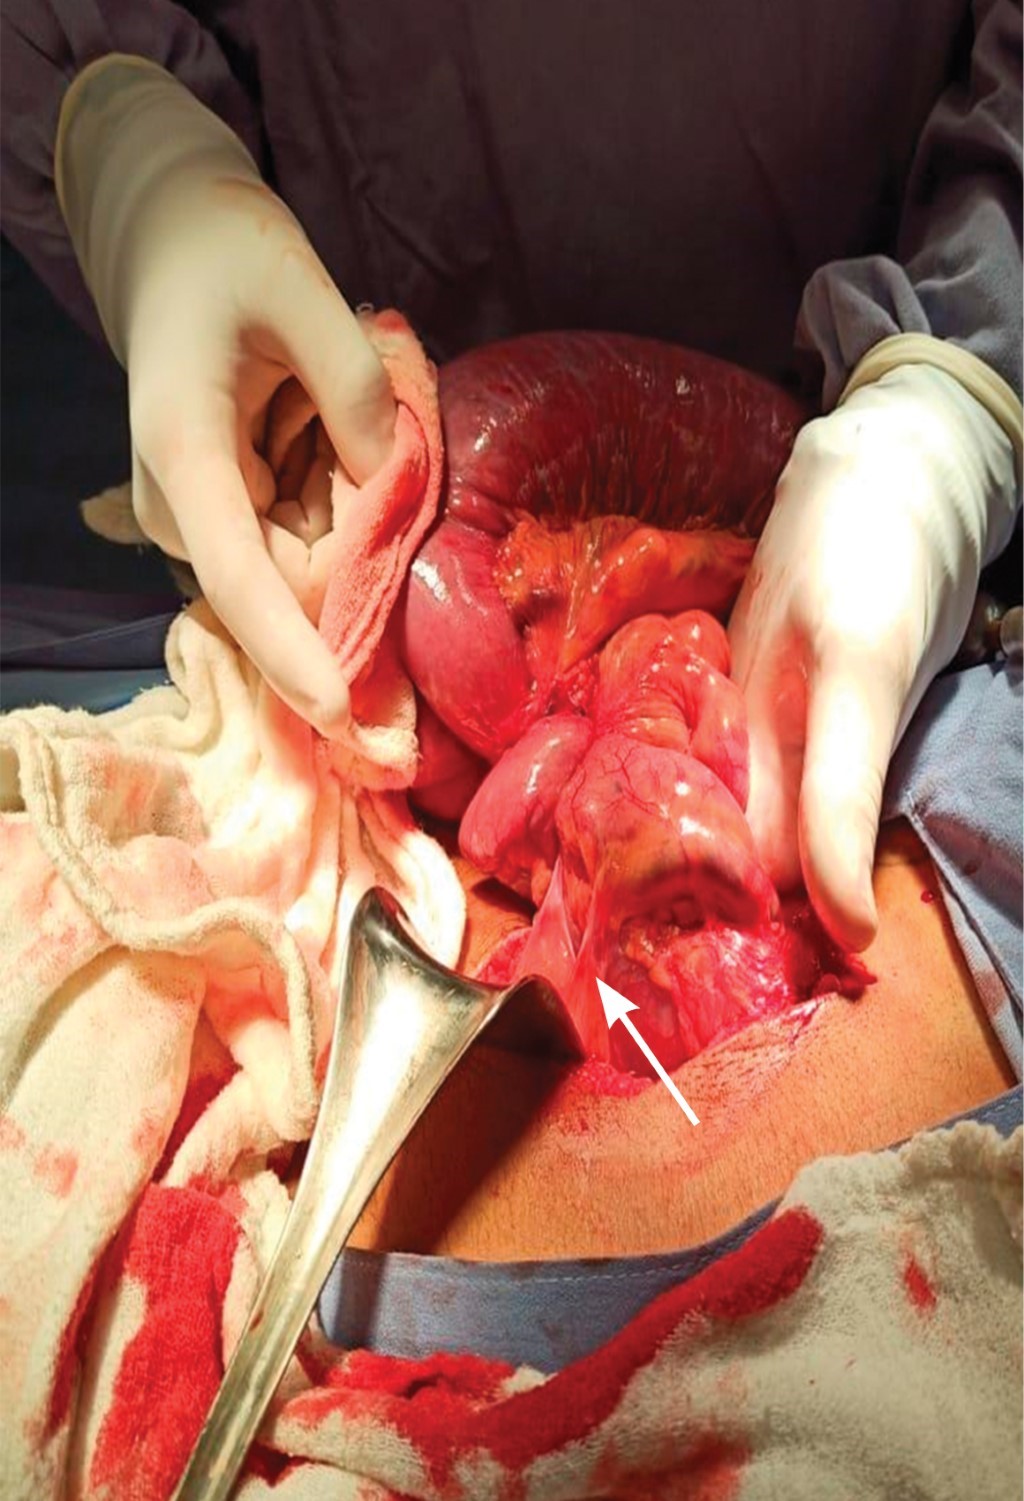

Los resultados de laboratorio se muestran en las Tablas 2, 3 y 4. La radiografía simple de abdomen en posición de pie muestra la presencia de distensión del intestino delgado, edema interasa con imagen en pila de monedas y niveles hidroaéreos, sin aire en colon (Figura 1). En la radiografía simple de abdomen en posición decúbito supino se aprecia el apilamiento de monedas y la presencia de imagen de burbujas duodenales (Figura 2).

Figura 1